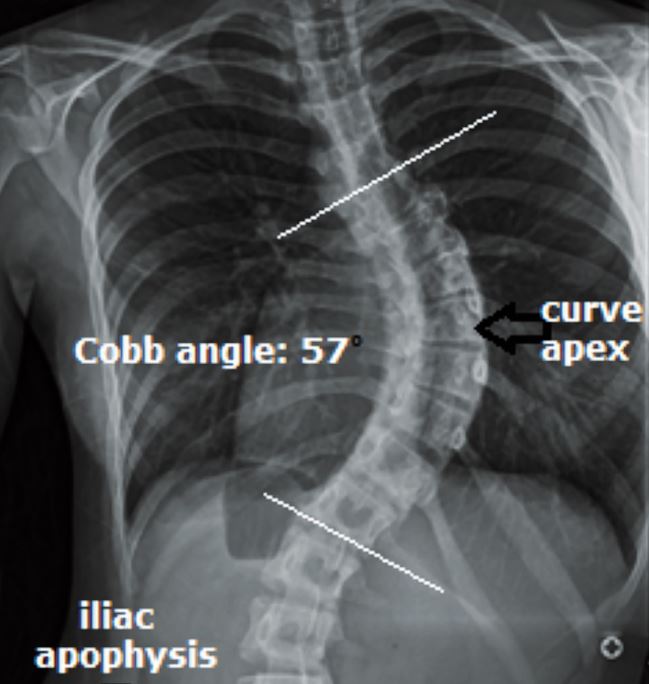

Abb. 2

Wirbelsäule mit Cobb-Winkel von 57°.